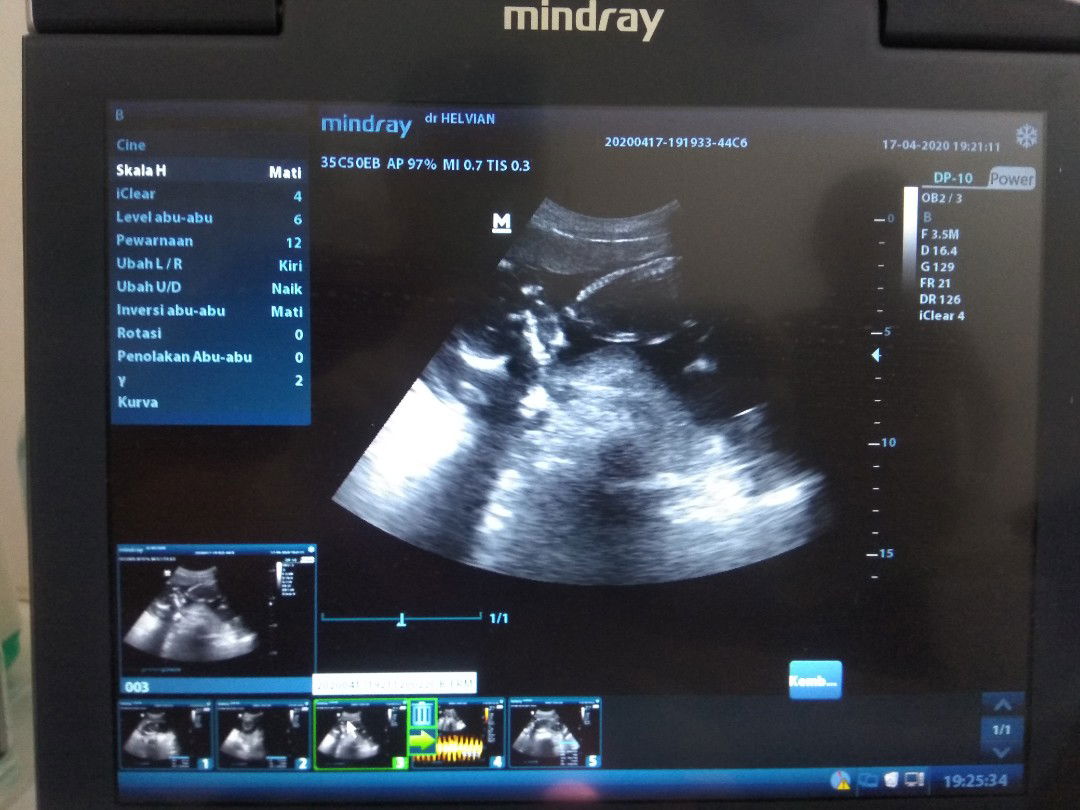

Kapan Harus Mulai USG?

Bun mau nanya dong, maklum kehamilan pertama.. Di usia kandungan berapa minggu ya, kita harus melakukan USG?